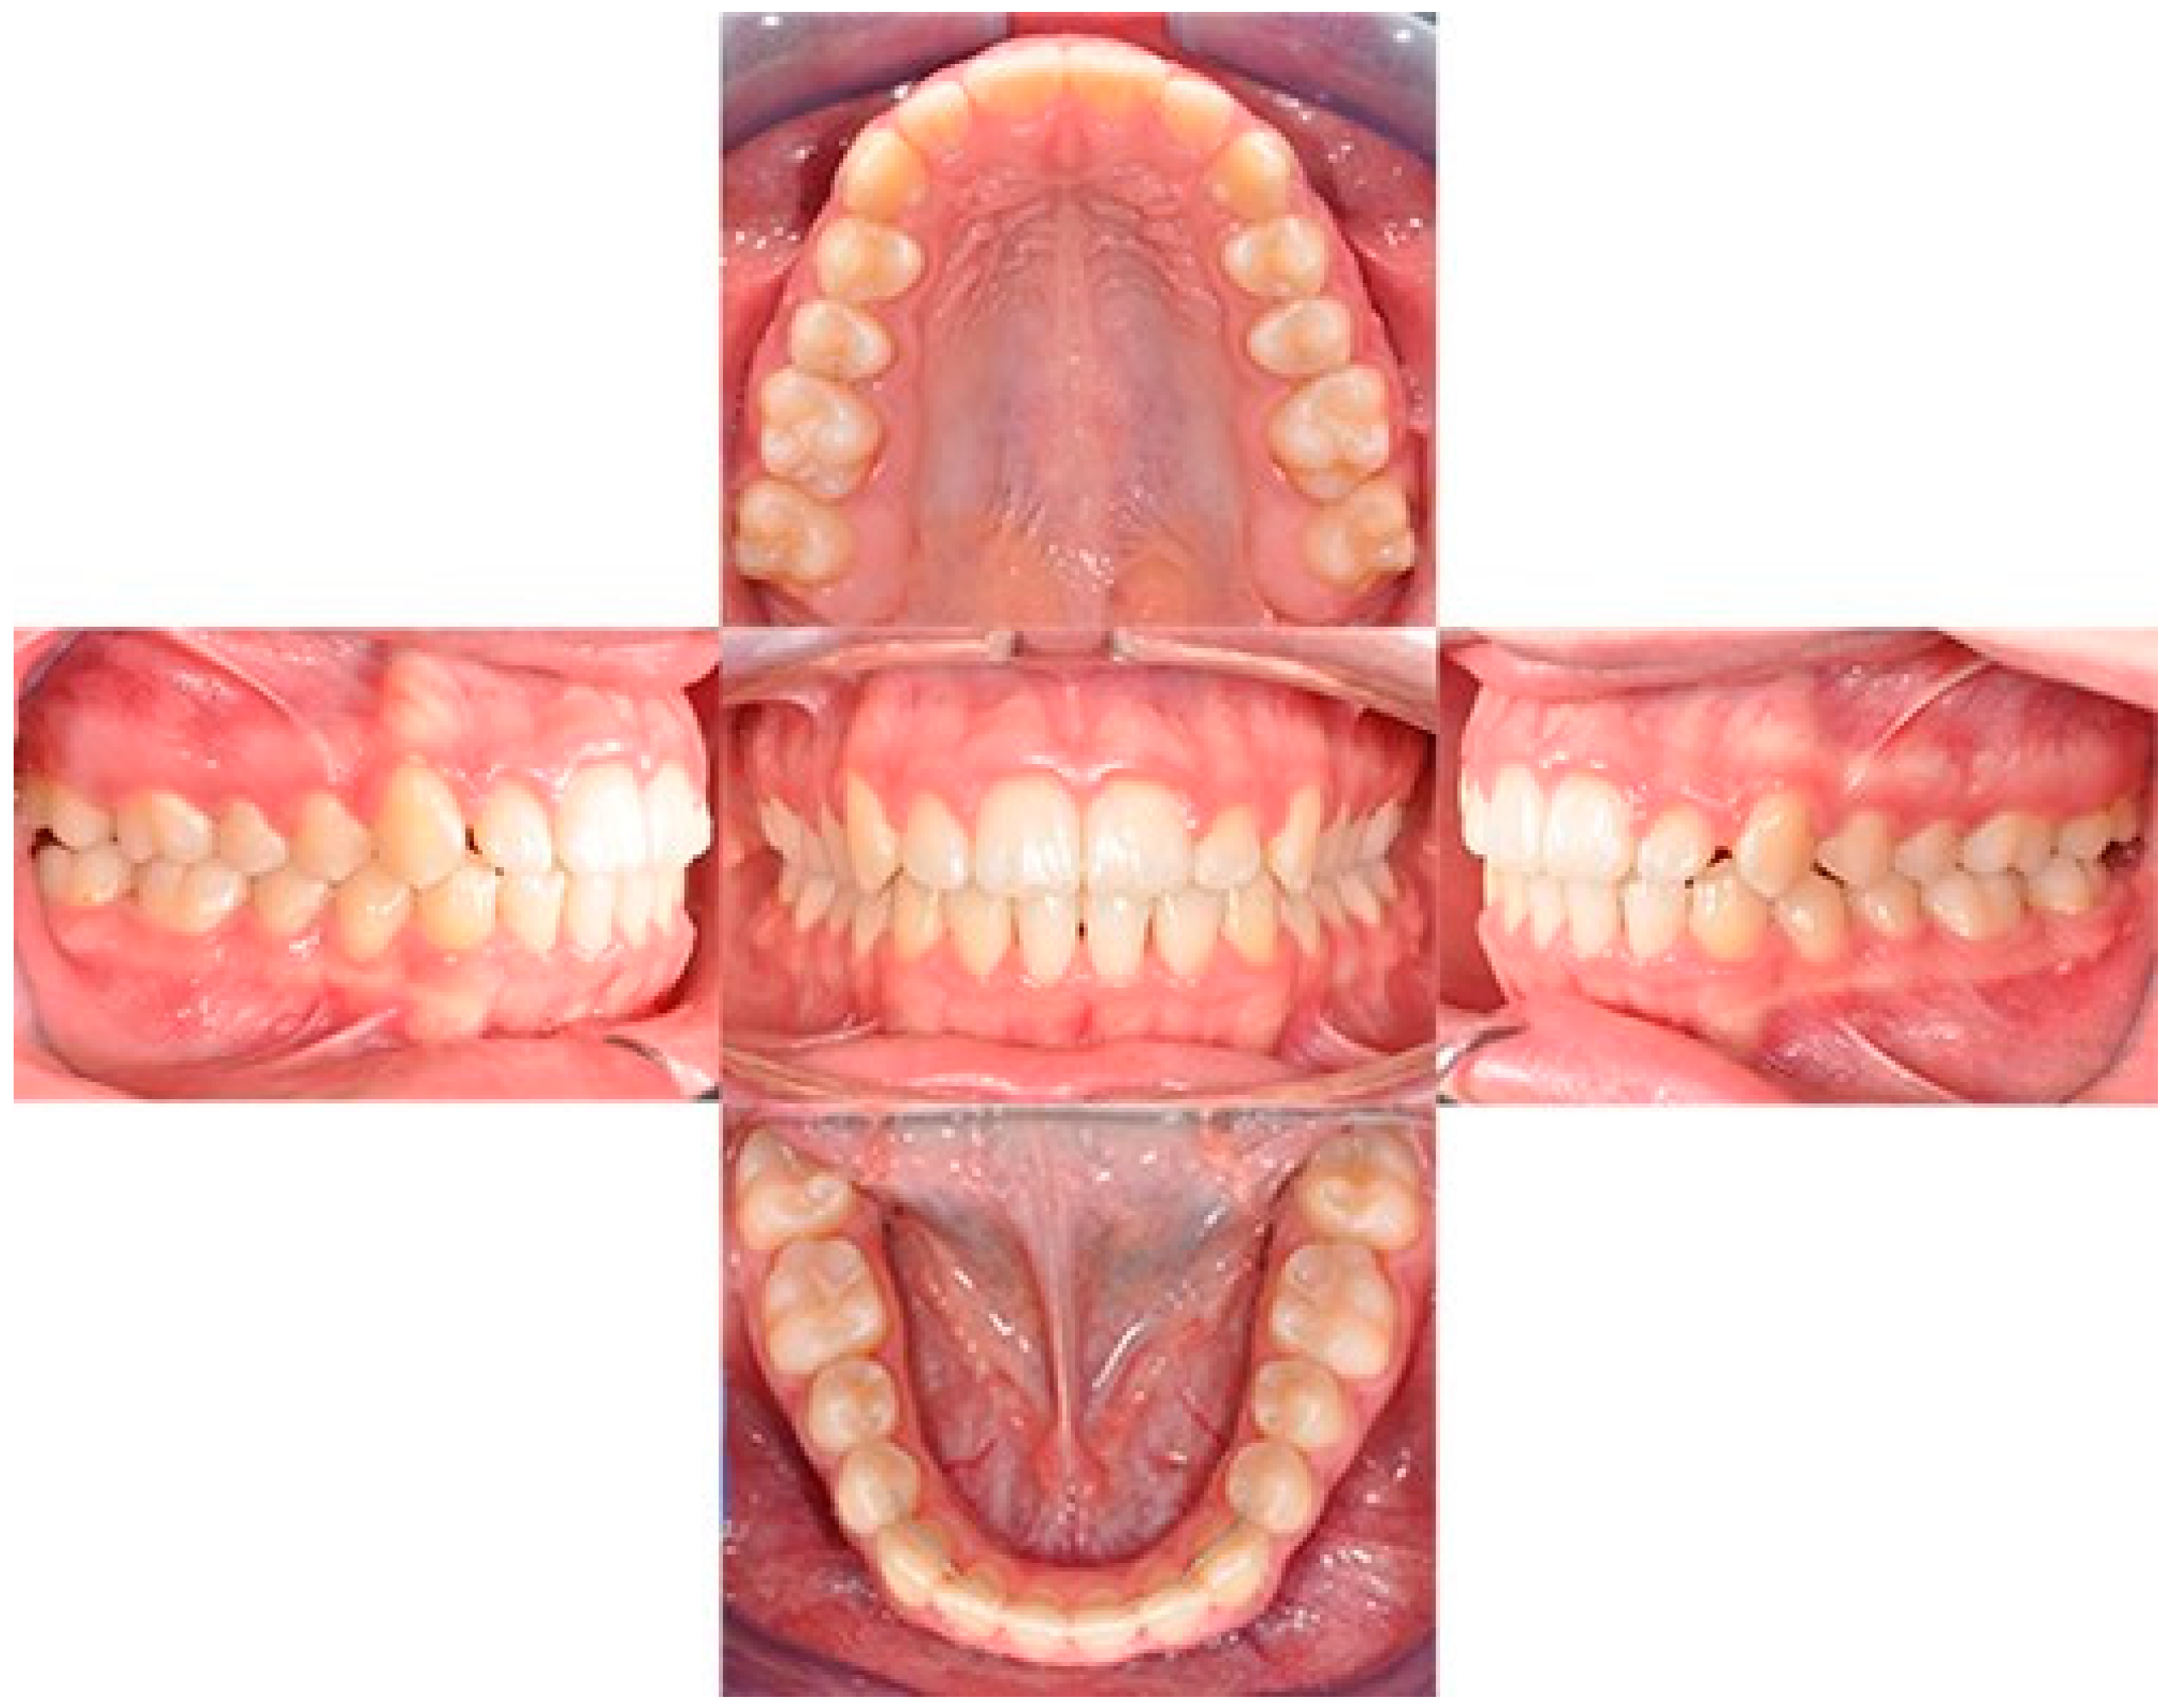

2. Case Report